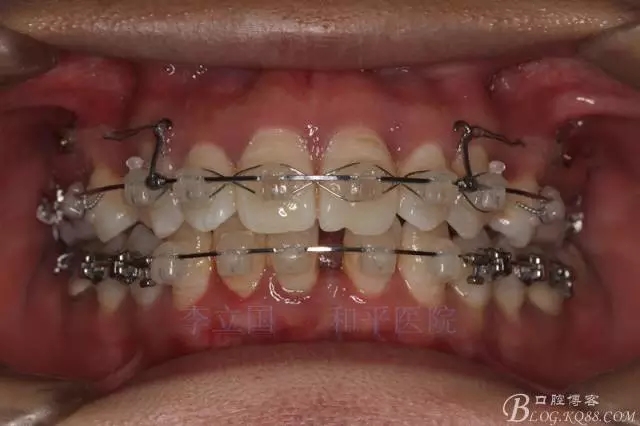

”嘴凸牙不凸”病例治療要點(diǎn)

患者主訴前突。

1.患者上前牙直立,面型前突,典型的嘴凸牙不吐,關(guān)鍵是前牙轉(zhuǎn)矩控制,建議使用高轉(zhuǎn)矩托槽。

4.使用長牽引鉤,使?fàn)恳咏项M骨阻抗中心,防止上頜骨的順時(shí)針旋轉(zhuǎn)。

5.回收過程中,上下前牙輕搖椅,防止覆合加深。